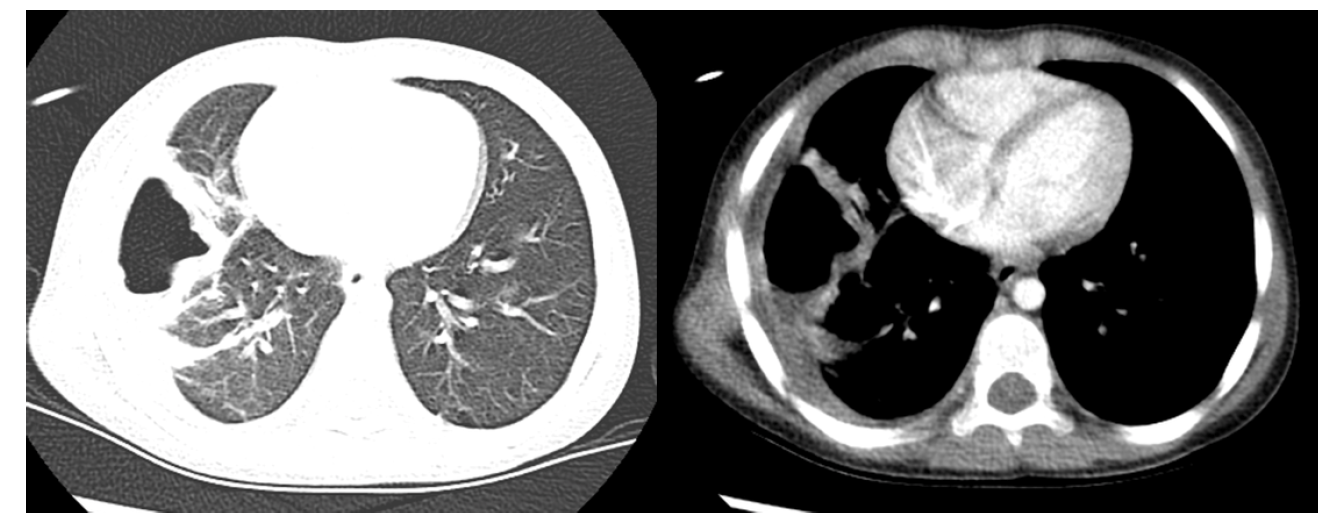

Adenocarcinoma

What is this?

Lung mets

Benign nodule